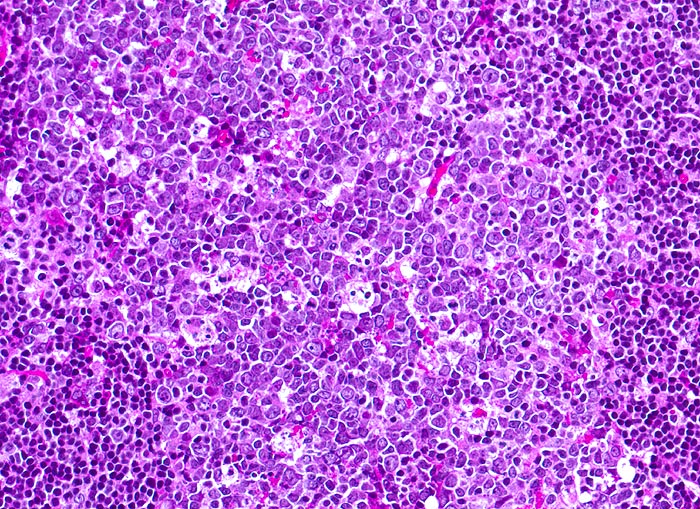

PathoPic – image database / PathoPic ID 4018 - infektiöse Mononukleose: follikuläre Hyperplasie

infektiöse Mononukleose: follikuläre Hyperplasie

Entzündung infektiös

Tonsille

Lymphatische Gewebe, KM, Milz

Tonsillektomie bei einem Studenten mit Angina, Lymphknotenschwellungen und einer Lymphozytose im Blut.

Histologie

200